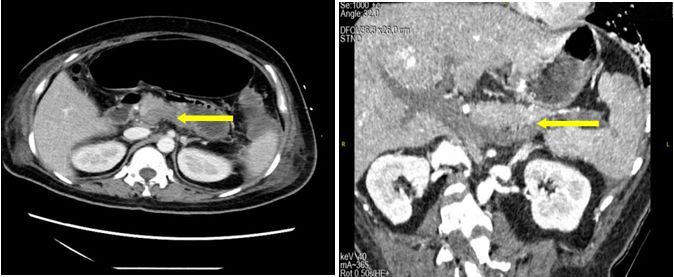

很快,腹部增强CT(见图B)和门静脉系统CTA(见图C)的结果回来了:

1.门静脉主干、右支及其属支密度减低,血栓形成可能;腹盆腔积液,小肠管壁增厚;

2.胆囊术后缺如;

3.孕期子宫;

4脂肪肝;

5.门静脉系统的广泛、完全的栓塞。

图B腹部增强CT(静脉期2018.04.15):门静脉、脾静脉未见造影剂充盈(红色箭头代表门静脉、黄色箭头代表脾静脉)

图C门静脉系统CTA(2018.04.15):门静脉、脾静脉、肠系膜上静脉未见造影剂充盈(红色箭头代表门静脉、黄色箭头代表脾静脉、绿色箭头代表肠系膜上静脉)